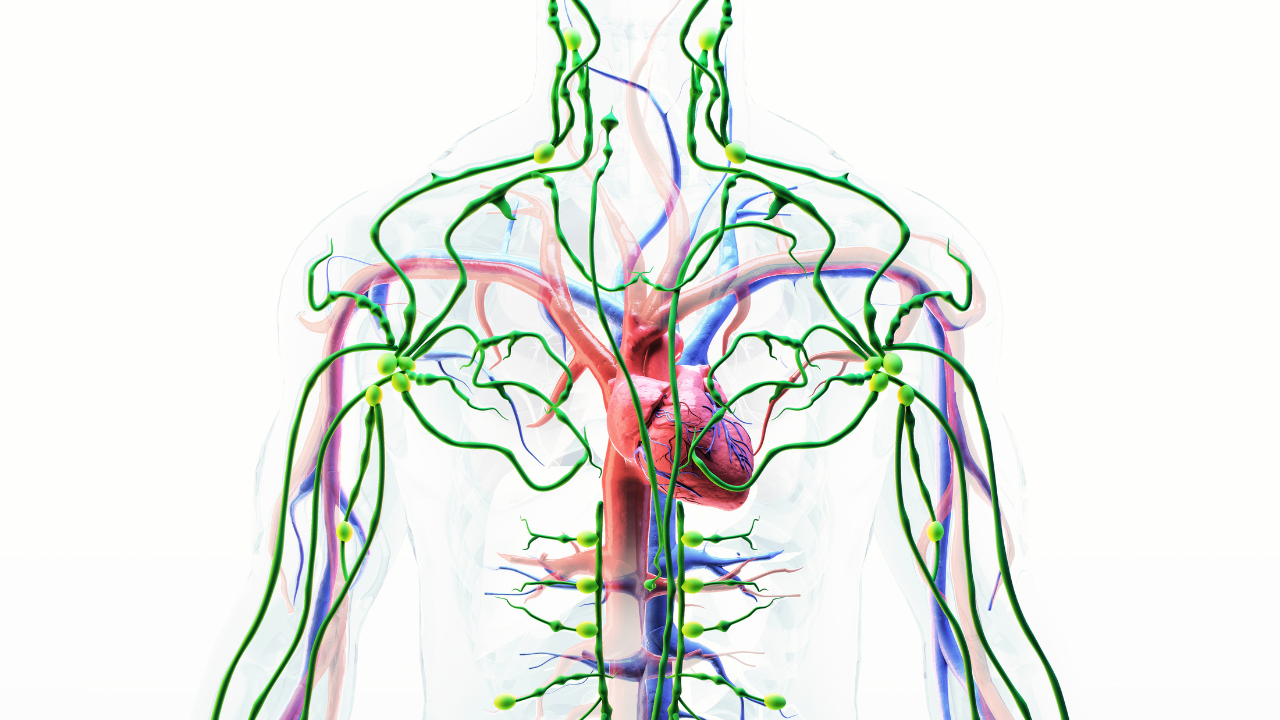

Our lymphatic system is similar to our body’s drainage and immune system. It assists in the movement of waste, toxins, and immune cells in the body. But when a person is under chronic stress, this system begins to disintegrate, getting tight, slow, and less efficient.

Let’s consider four actual ways that stress impacts your lymph vessels based on research.